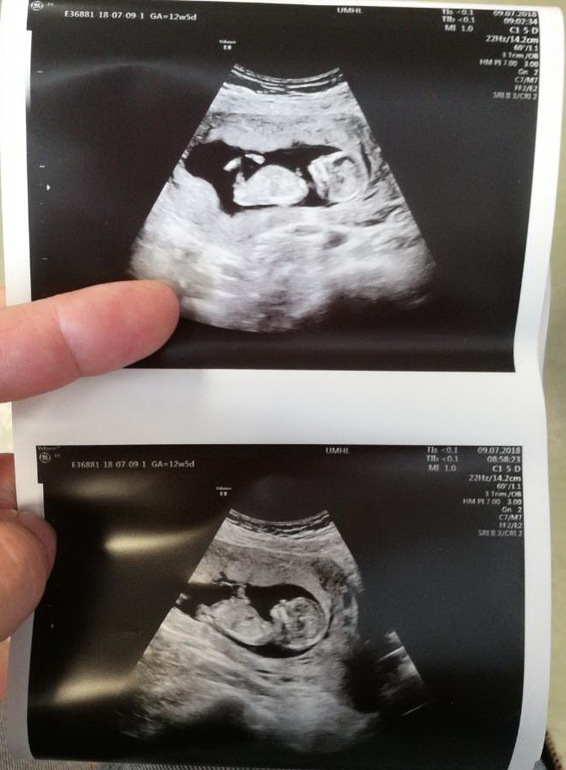

12+5

2018Была сегодня на скане. Ура!

Малыш в порядке!!! Слава Богу. Теперь можно робко начинать радоваться и строить планы! До сих пор боялась.

Чувствую себя хорошо, давление немного повышенно 134 на 96. Очень счастлива!!!))

Следующий скан в 28 недель, 22 октября. Долго, не дождусь наверно, пойду на платный, недель в 20, узнать пол.